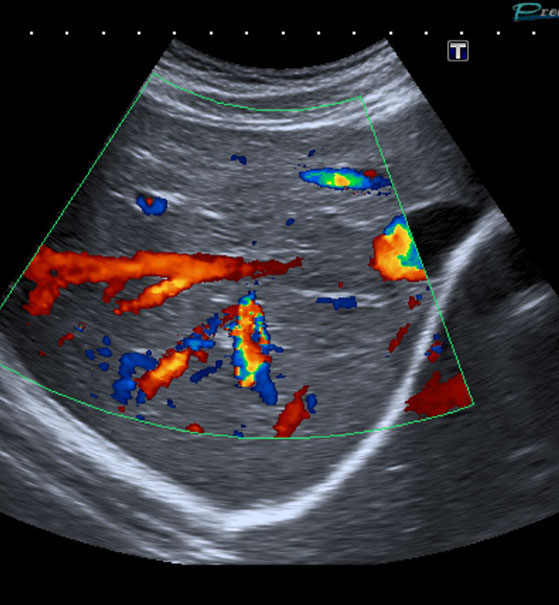

• Die großen Bauchgefäße (speziell Bauchschlagader) zur Erfassung von Gefäßaussackungen (Aneurysmen) oder Engstellen (Stenosen) sowie bei Verschlüssen, Thrombosen der Pfortader und anderer Bauch- und Beckengefäße.